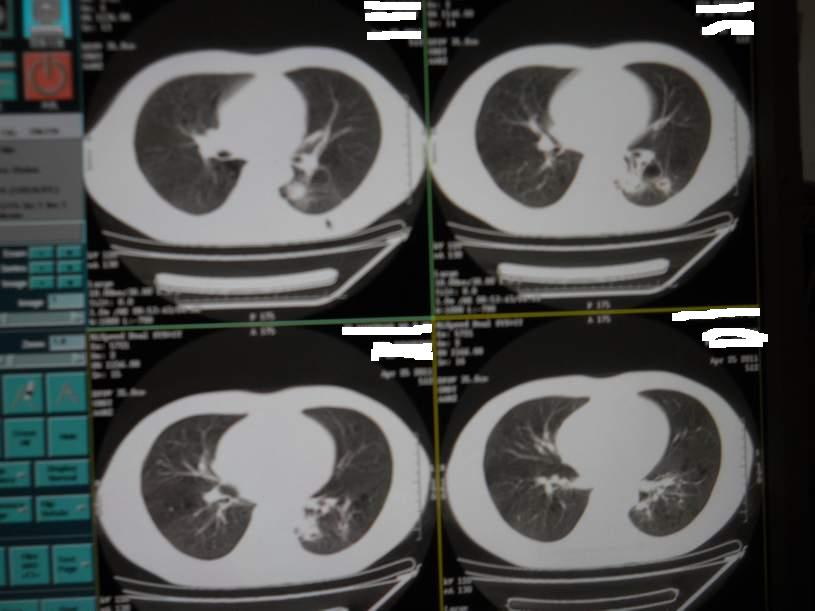

肺霉菌感染

男,22岁,一年前诊断马尔菲尼青霉菌感染,多次复查CT。多次HIV阴性。最近两次CT图片。有实验室结果。

最近实验室检查结果:霉菌感染。